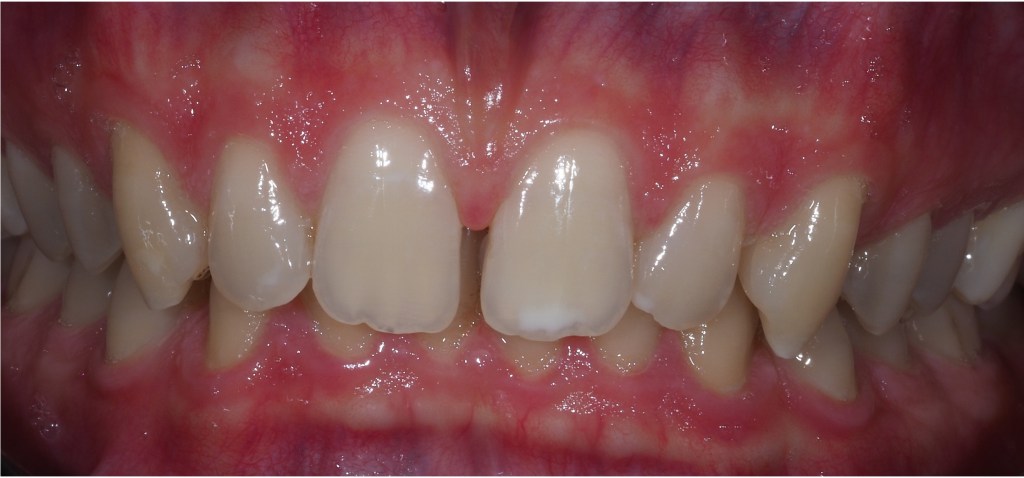

Composite bonding can also be carried out to close spacing and change the colour of teeth particularly when orthodontic treatment is not desired and tooth whitening has been attempted.